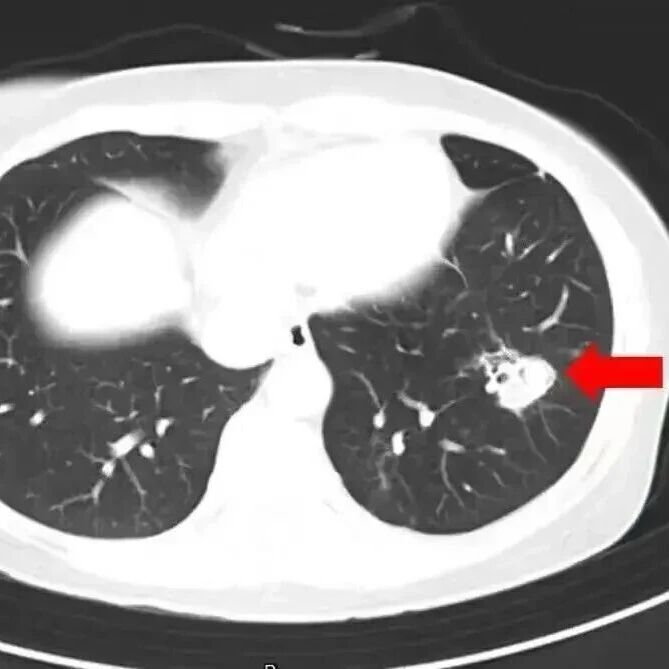

2025年1月,江苏扬州的张大爷为迎接春节开始大扫除,清扫过程中不慎吸入大量灰尘和霉菌孢子,导致哮喘发作。张大爷随即服用了常备的哮喘治疗药物,可症状反而逐渐加重。经检查,张大爷的肺部出现感染,确诊为肺曲霉病。

北京佑安医院感染综合科主任医师李侗曾介绍,对于免疫力低下的人,吸入了这些真菌,就会发病引起肺部的病变——曲霉肺炎。因为它是通过呼吸道感染的,进入血液后是可以扩散到全身。大脑因为血供最丰富,所以也是真菌最容易侵犯的器官。